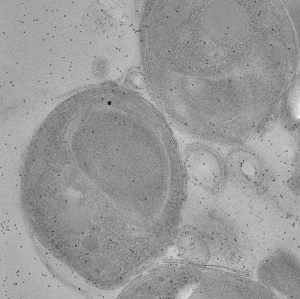

Malaria-infected red blood cell section showing schizont stalled in egress with the inhibitor E64

Sample Organism: Plasmodium falciparum 3D7

Sample: Plasmodium falciparum infected human erythrocyte treated with the egress inhibitor E64

Parasitophorous vacuole poration precedes its rupture and rapid host erythrocyte cytoskeleton collapse in Plasmodium falciparum egress.

Hale VL , Watermeyer JM, Hackett F, Vizcay-Barrena G, van Ooij C, Thomas JA , Spink MC, Harkiolaki M, Duke E, Fleck RA , Blackman MJ, Saibil HR

(2017) PNAS , 114 , 3439 - 3444